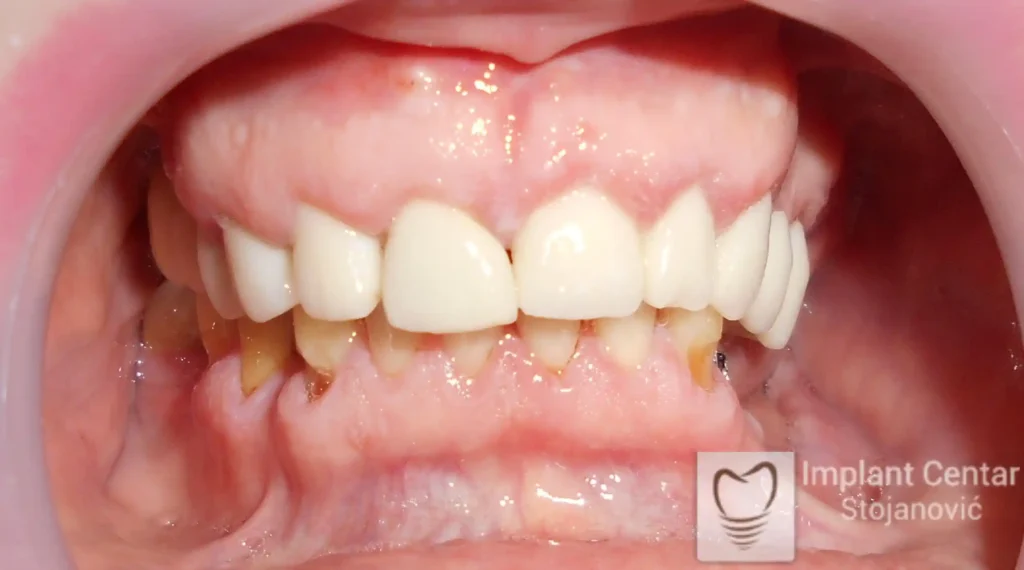

Na slikama 1, 2, 3 , 4  i  5 prikazan je izgled pacijenta pre početka terapije. Nakon detaljne kliničke i radiološke analize, doneta je odluka o vađenju zuba loše biološke vrednosti, dok su bezuba polja sanirana ugradnjom dentalnih implantata.

Nakon ugradnje implantata i pripreme preostalih zuba, pacijentu su izrađene fiksne privremene krunice, čime je postignut eugnatan zagriz već nakon jednog dana (slika 8, 9 i 10). Tokom perioda osteointegracije, pacijent se postepeno privikavao na novi položaj vilica i zagriz.

Po završetku perioda integracije, izrađeni su definitivni cirkonijum-keramički mostovi, čime je postignuta potpuna rekonstrukcija zagriza, kao i značajno poboljšanje estetike i oralne funkcije (slika 12, 13, 14 i 15).